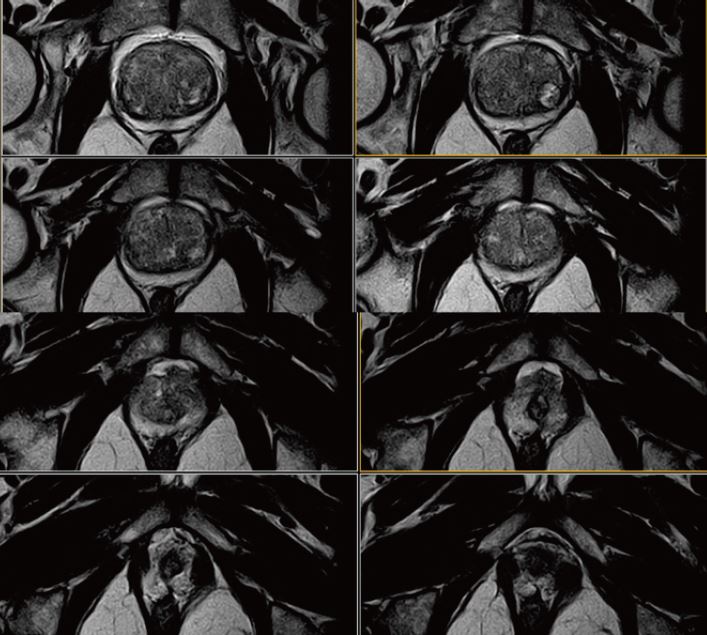

Рис. 2. Аксіальне, Т2-зважене зображення (за протоколом mpMR).

Рис. 3. Аксиальне DWI – A=b0, B=Iso b800, C=Iso b1000 e, D=Iso ADC (за протоколом mpMR)